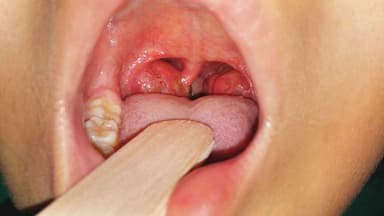

Tại Thu Cúc TCI, chị H được Trưởng phòng khám TMH, TTUT. BS. Dương Văn Tiến thăm khám. Qua khai thác tiền sử bệnh lý và nội soi tai mũi họng, bác sĩ Tiến xác định: “Bệnh nhân H bị viêm Amidan mạn tính quá phát độ 4, rất nhiều hốc bã đậu. Đây là nguyên nhân dẫn đến tình trạng tái phát viêm Amidan nhiều lần trong năm. Viêm Amidan mãn tính có nên cắt không? Thông thường, đối với các bệnh nhân lớn tuổi, việc chỉ định cắt viêm Amidan cần hết sức đắn đo. Chúng tôi ưu tiên vừa điều trị viêm hiệu quả vừa bảo tồn nguyên vẹn Amidan. Tuy nhiên, trường hợp của bệnh nhân H, bắt buộc phải phẫu thuật, do công việc và cuộc sống của bệnh nhân đã và đang bị ảnh hưởng quá trầm trọng. Không những thế, đôi khi, viêm Amidan mạn tính có thể tiến triển đến áp xe, viêm mô tế bào Amidan, viêm phổi, viêm phế quản, viêm khớp cấp, viêm ngoài màng tim, viêm cầu thận, viêm màng não, nhiễm khuẩn huyết,… rất nguy hiểm!”.